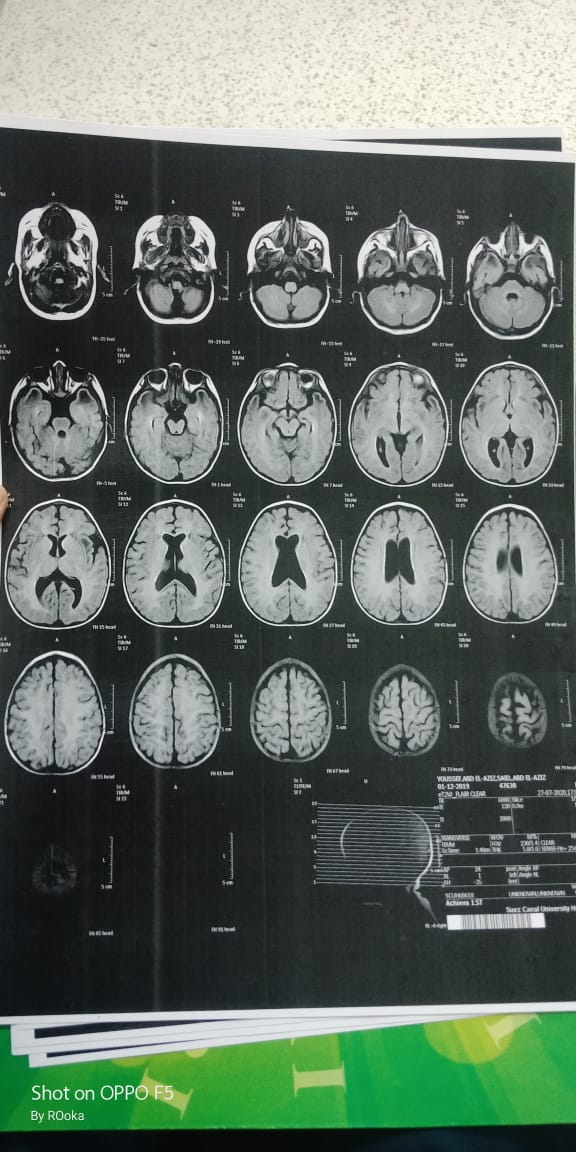

وأضاف عبد العزيز، في تصريحات خاصة لـ القاهرة 24: اكتشفنا مرض يوسف وهو عنده 6 شهور، طلع عنده نقص في المادة البيضاء، ونقص في الأكسجين، مع تآكل في القشرة المخية.

وأكد أن طفله فاقد للحركة والكلام حاليًا، مع تمدد حجم الدماغ، نتيجة معاناته من اختلالات عصبية، التي تنشأ عن المرض، معقبًا: الطفل يحتاج لجهاز طبي يساعد على تخفيف حدة الأعراض، وفقًا لاستشارة الأطباء.